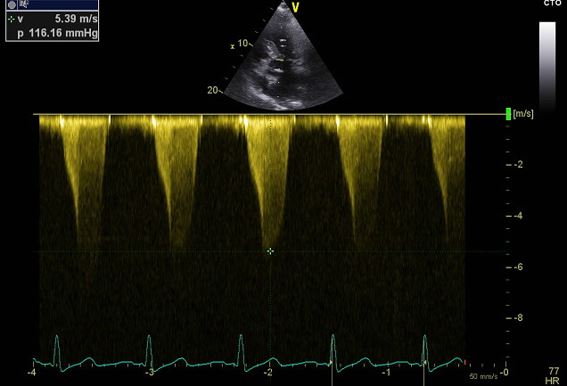

The patient was admitted to the emergency department with acute heart failure with clinical worsening during the last two days. In addition, she presented with cough, expectoration and fever up to 39ºC.  An echocardiogramme on arrival confirmed the known asymmetric hypertrophy of the basal interventricular septum (18 mm), and a severe worsening of the left ventricular outflow tract obstruction (120 mmHg) together with SAM and moderate to severe mitral regurgitation (Figure 1)

Fig 2 CC - Clinical Case - hypertrophic cardiomyopathy.jpg